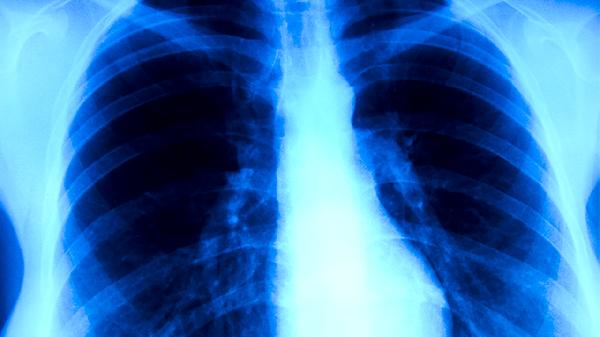

肺結(jié)核主要由結(jié)核分枝桿菌感染引起,常見病因包括免疫力低下、密切接觸傳染源、合并慢性病、營養(yǎng)不良、長期使用免疫抑制劑、居住環(huán)境擁擠、職業(yè)暴露及既往結(jié)核感染未徹底治愈。肺結(jié)核屬于法定乙類傳染病,需規(guī)范抗結(jié)核治療并做好隔離防護(hù)。